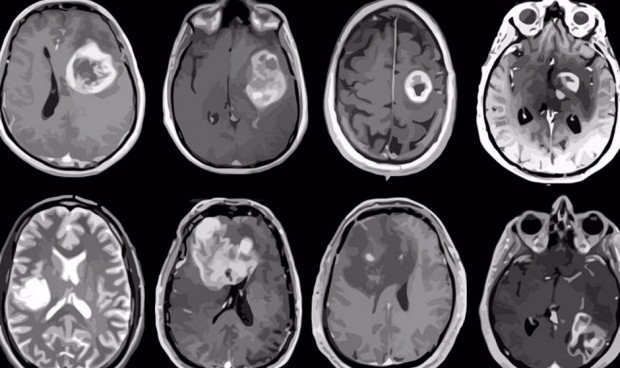

Una nueva vacuna de ARN mensajero fabricada en la Universidad de Florida contra el cáncer ha permitido reprogramar el sistema inmunológico del humano para poder atacar al tumor cerebral más agresivo de todos, el glioblastoma. Este nuevo abordaje ya se ha testado en un ensayo clínico en humanos, concretamente con cuatro pacientes adultos, logrando un resultado más que prometedor.

Una de las principales novedades de la vacuna es que usa células tumorales propias del paciente, con el fin de crear una vacuna personalizada. El principal resultado cosechado hasta la fecha es que la vacuna permitió estimular una respuesta del sistema inmunológico del paciente para contraatacar el tumor.

Tras su administración, los cuatro pacientes que sufrían un tumor cerebral lograron vivir libres de la enfermedad más tiempo del pronosticado. En concreto, los 10 perros vivieron una media de 139 días, cuatro veces más de lo habitual en estos casos.